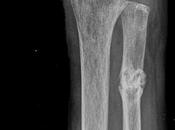

Pseudoartrosis por fractura antigua a nivel del tercio proximal de cubito...

RADIOGRAFIA DE ANTEBRAZO IZQUIERDOTECNICA: Proyección AP y LateralHALLAZGOS: • Solicion de continuidad con engrosamiento irregular de la cortical ósea de... Leer el resto

Fractura a nivel de radio distal a nivel de metáfisis con fragmento distal...

RADIOGRAFIAS AP Y LATERAL DE MUÑECA Hallazgos: -Radio en porción distal con presencia de fractura de metáfisis por trayecto trasversal, con área distal oblicua... Leer el resto